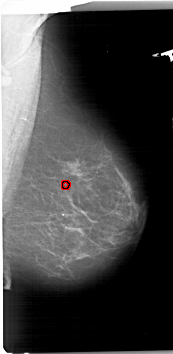

A_1740_1.RIGHT_CC

FILE: A_1740_1.RIGHT_CC.OVERLAY

TOTAL_ABNORMALITIES 1

ABNORMALITY 1

LESION_TYPE CALCIFICATION TYPE PLEOMORPHIC DISTRIBUTION CLUSTERED

ASSESSMENT 4

SUBTLETY 2

PATHOLOGY BENIGN

TOTAL_OUTLINES 1

BOUNDARY